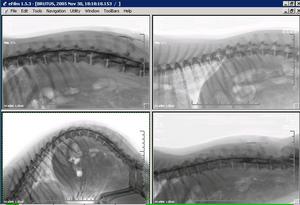

NEURORADIOGRAFÍA: En neurología es de gran ayuda muchas veces el realizar copias en negativo para la observación de los contrastes mielográficos. |

OTROS FORMATOS DE IMPRESIÓN: |